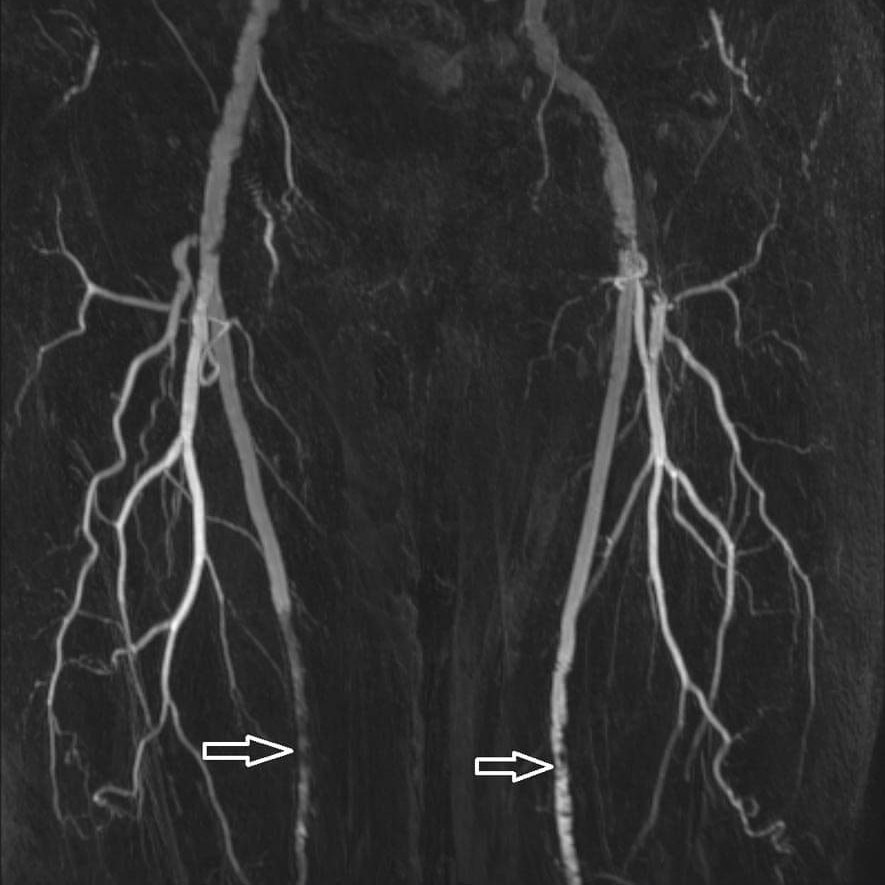

Anatomie

Normale Anatomie der Beinarterien.